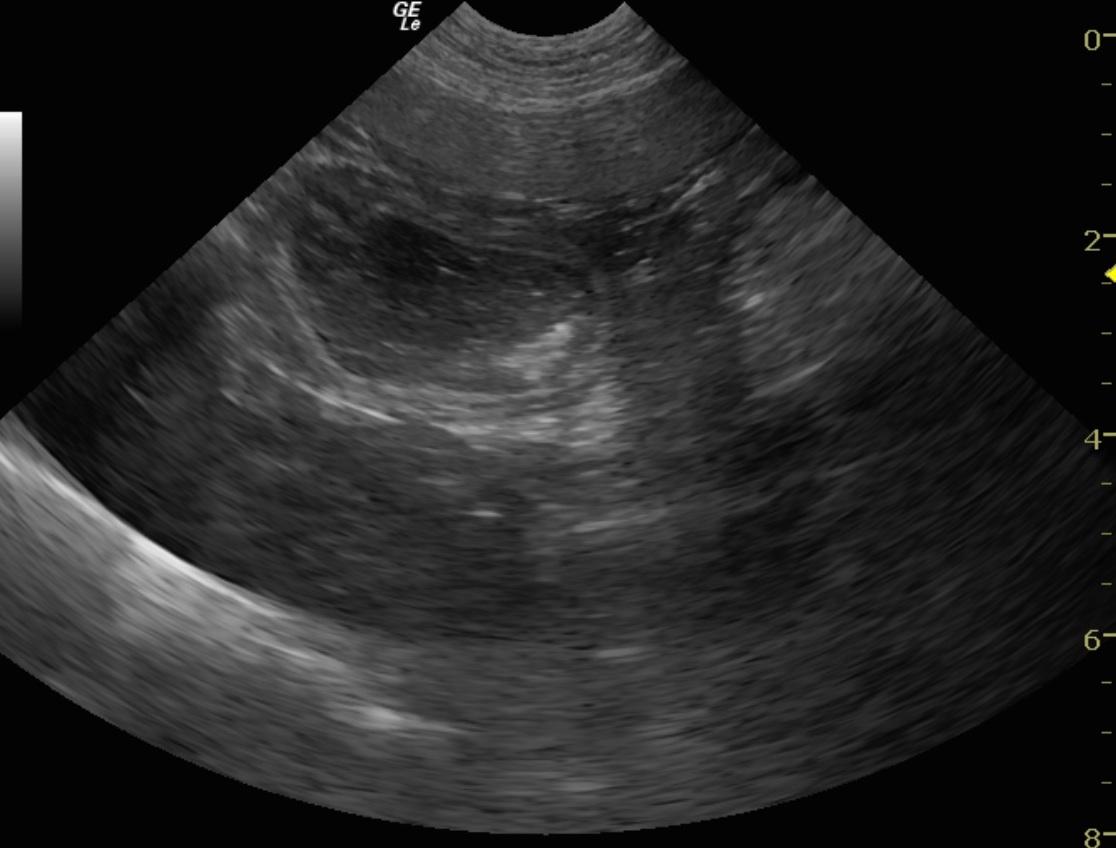

An 8-month old MN Cockapoo dog was presented with a history of vomiting, diarrhea, anorexia, lethargy, and painful abdomen. Leukocytosis was present on CBC, whereas serum biochemistry panel was within normal limits.